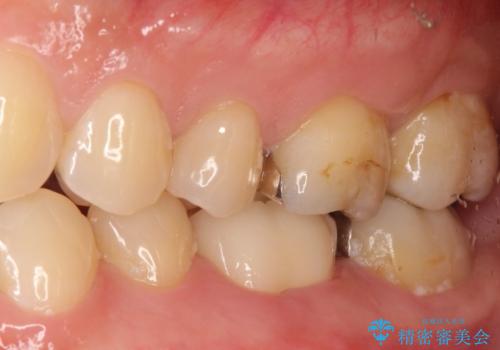

- 噛んだ時の痛みを主訴に当院受診されました。

根管治療を行なったのち、症状改善を認めオールセラミッククラウンにて修復治療を行なっております。

┌7は今回の治療後打診(-)、正常歯髄へ診断のもと経過観察を行なっております。